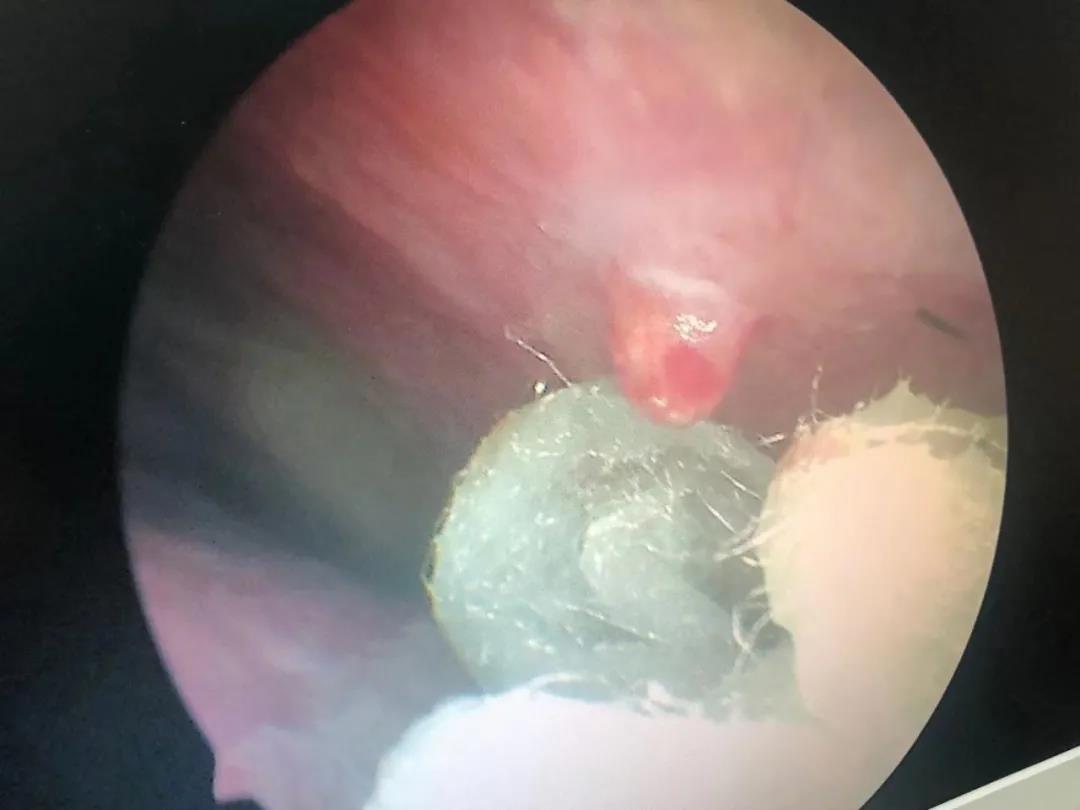

“你這個(gè)不是鼻中隔偏曲啊,是血管瘤造成的,你看這里有一個(gè)血管瘤”。耳鼻喉科專家黃定強(qiáng)博士通過鼻內(nèi)鏡檢查發(fā)現(xiàn),吳大叔鼻腔內(nèi)有一顆約黃豆大小的血管瘤。

(吳大叔鼻內(nèi)鏡下血管瘤)